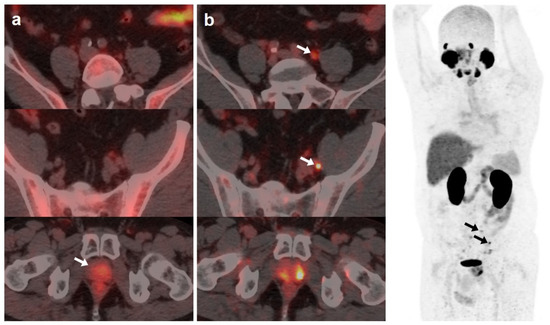

59-year-old patient. Gleason 7 PCa treated with radiotherapy plus ADT. After ADT withdrawal BCR was detected (PSA 2.44 ng/mL, PSAdt 2.6 months, PSAvel 0.15 ng/mL/month). [18F]F-choline (a) demonstrated only prostatic uptake (white arrow) and [18F]DCFPyL-PET/CT (b) showed prostatic tracer uptake and lymph nodes metastases (white and black arrows). Time window of sixteen days between both scans. [18F]DCFPyL changed therapeutic management allowing escalation (ADT + Apalutamide).

On the other hand, [18F]DCFPyL was positive alone in 48/89 (53.9%) patients, being oligometastatic in 25 (Figure 2). Five patients were exclusively positive with [18F]F-choline-PET/CT, and thus, [18F]DCFPyL down-staged [18F]F-choline results from positive to negative (3 follow-up, 1 biopsy (negative) and 1 ADT). [18F]DCFPyL up-staged 5/21 patients with oligometastatic disease on [18F]F-choline-PET/CT to polimetastatic disease after [18F]DCFPyL.